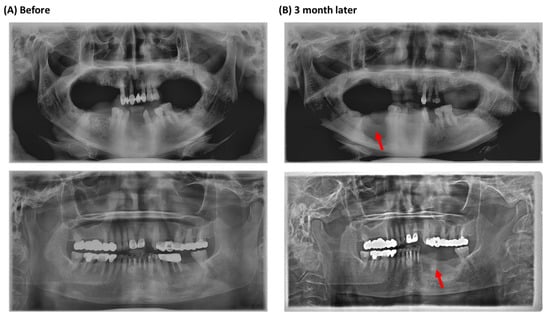

3.1. Clinical Findings